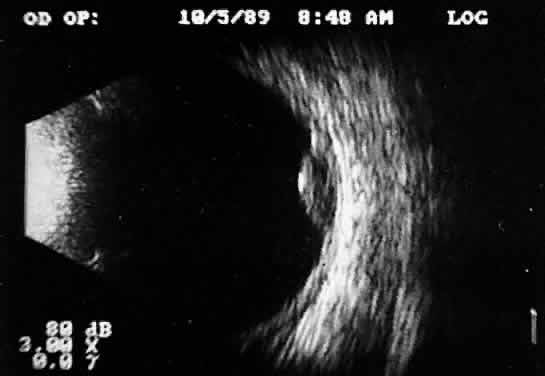

is an important measurement for initial and follow-up examination.10 TUMORS A-scan tumor characterization is often extremely helpful to the clinician. A thorough understanding of ophthalmic pathology is critical to interpretation and often predictive of typical A-scan tumor patterns. Choroidal malignant melanoma, perhaps the most widely studied intraocular mass lesion, has the most reproducible and reliable A-scan pattern. Usually, the initial echo seen in A-scan is a high-amplitude spike secondary to the strong vitreoretinal surface echo overlying the tumor mass. Once the examining sonic beam has passed into the tumor tissue, a rapidly declining amplitude cadence is noted, a consequence of increasing ultrasonic tissue homogeneity. Clinical knowledge of the typical microscopic tumor pattern of tightly packed, homogeneous small cells makes anticipation of relatively low reflectivity possible (Fig. 10). This same low-amplitude reflectivity in B-scan imaging produces a picture that makes the melanoma mass appear hollow. Often, tumor-infiltrated choroid also appears dark (Fig. 11). This change in the normally highly reflective choroidal tissue is widely but inaccurately called choroidal excavation. The terms “hollowing” and “choroidal excavation” are misleading because these tumors are not hollow and the choroid is not excavated. Nevertheless, these terms have been used so frequently in past literature that any change in vocabulary is unlikely.

Tumors with great acoustic heterogeneity, such as choroidal hemangiomas, where adjoining cell and tissue layers have marked differences in acoustic impedance, create large echo amplitudes at each interface. These tumor types have typical high internal reflections at each major interface. These high internal reflections make the lesions appear solid white in B-scan displays and produce highamplitude spikes during A-scan imaging (Fig. 12).